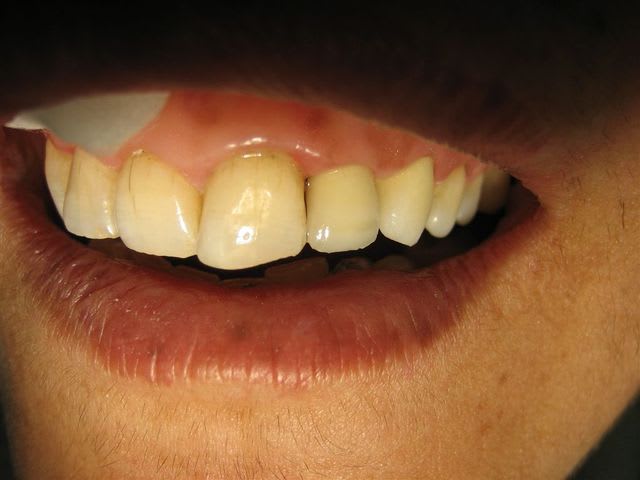

Très joli boulot.

Tout est en harmonie avec l'âge du patient, les embrasures, les surfaces de contact, le plan incisif.

Vraiment très réussi.

Si tu as le résultat en bouche, je suis preneur.